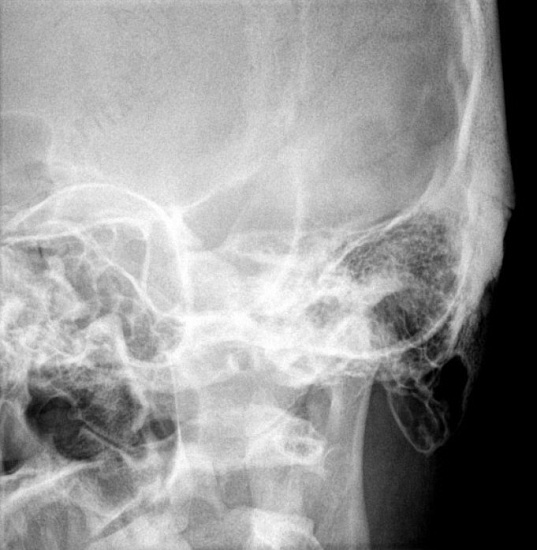

Рентгенография сосцевидных отростков – важный метод прицельного исследования сосцевидных отростков.

Диагностическая услуга выполняется в одной/двух проекциях. Сосцевидные отростки – выступы костей, которые расположены на боковых сторонах позвонках. Они играют важную роль в поддержании стабильности позвоночника и защите спинного мозга.

• подозрение на острый гнойный воспалительный процесс;

• для исключения мастоидита;

• для исключения костно-травматической патологии.